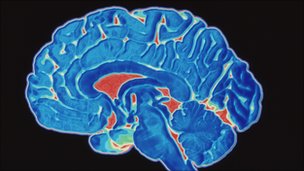

Let’s start by taking a look at the latest scientific research which has shown that the practice of meditation actually changes the shape of the brain, allowing specific areas in the brain to grow or change. This finding has established a new field of contemplative neuroscience – the brain science of meditation – and helps to explain how meditation acts to improve brain function and mental health.